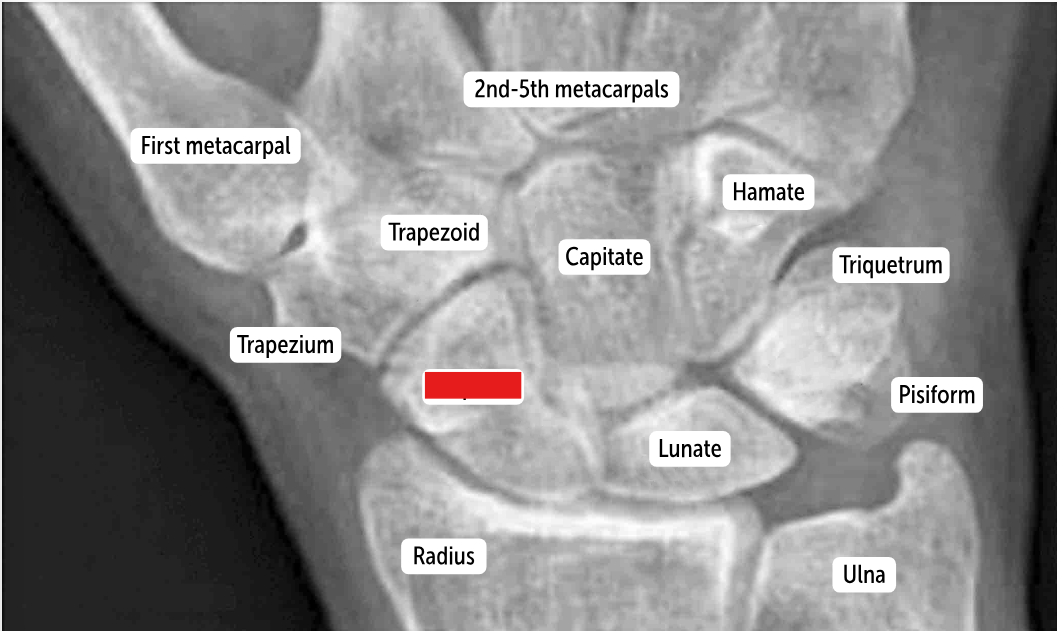

The most commonly fractured carpal bone by falling on an outstretched hand, which has a risk of avascular necrosis, is the __________.

Scaphoid bone

The most commonly dislocated bone after a fall on an outstretched hand is the ___________.

Lunate bone

Carpal bones by row:

So Long To Pinky, Here Comes The Thumb

Scaphoid, Lunate, Triquetrum, Pisiform, Hamate, Capitate, Trapezoid, Trapezium

Scaphoid

Lunate

Triquetrum

Pisiform

Hamate

Capitate

Trapezoid

Trapezium

Which carpal bones articulate with the metacarpal bones?

The bones of the distal row (hamate, capitate, trapezoid, and trapezium) articulate with the metacarpal bones.